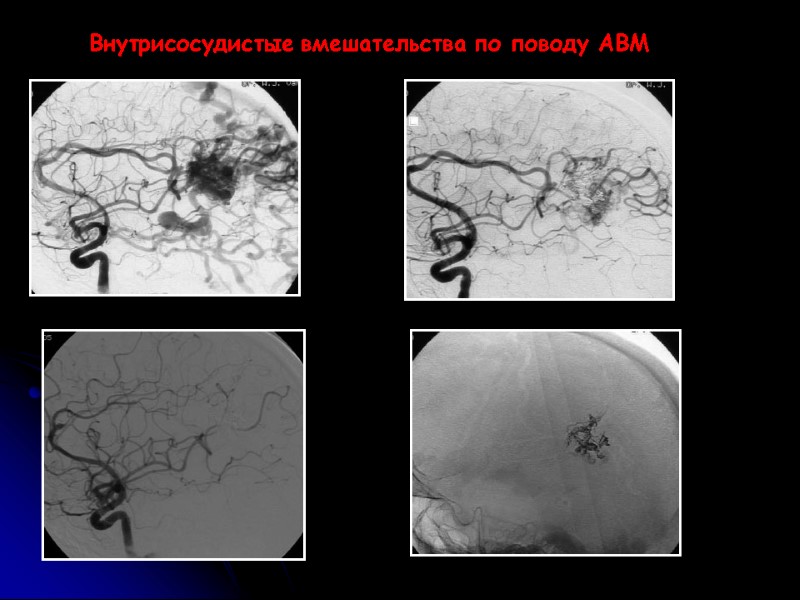

Артериовенозные мальформации дебют до 40 лет; 2% от всех инсультов - 300 000 пациентов в США; дебют 30 – 82% АВМ в виде геморрагического синдрома Открытые и внутрисосудистые вмешательства

Внутрисосудистые вмешательства по поводу АВМ